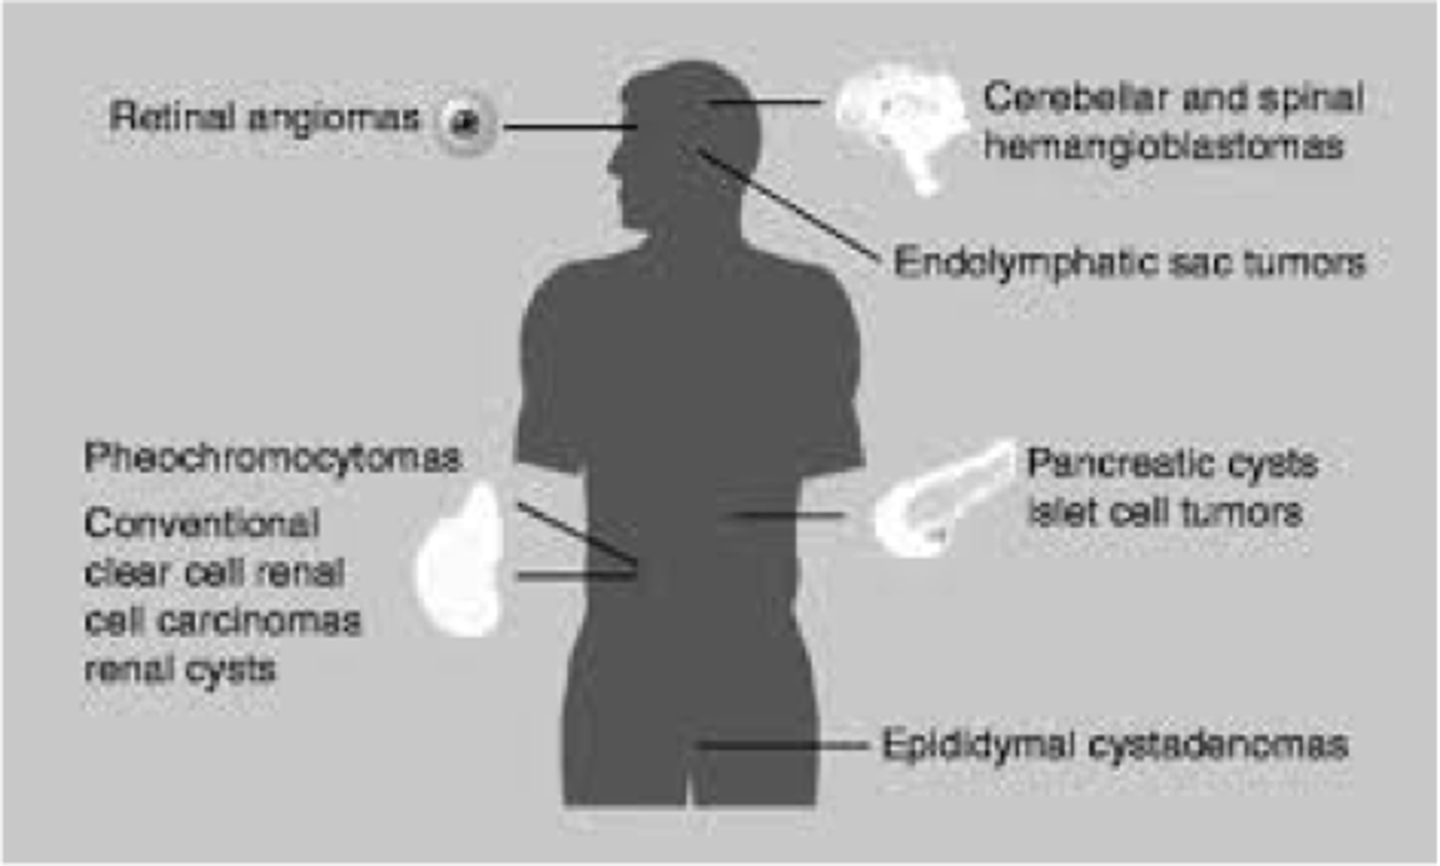

Renal cell carcinoma (bilateral), hemangioblastomas in retina/spine, angiomatosis, pheochromocytoma

von Hippel-Lindau disease (dominant tumor suppressor gene mutation)